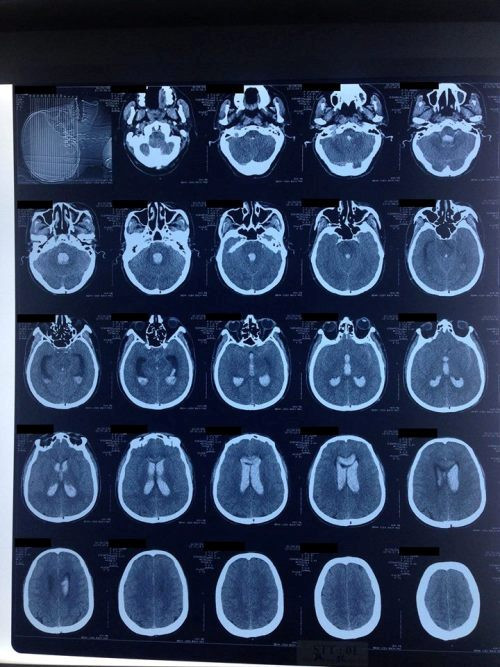

Khoảng 9 giờ sáng ngày 26 tháng 2 năm 2017, bệnh nhân đột ngột đau đầu dữ dội, sau đó nhanh chóng rối loạn ý thức, được gia đình đưa vào Bệnh viện Đa khoa tỉnh Hải Dương trong tình trạng hôn mê sâu (GCS 5 điểm), ứ đọng hầu họng nhiều và không rõ liệt. Bác sĩ trực đã nhanh chóng tiến hành cấp cứu, đặt ống nội khí quản và thở máy cho bệnh nhân. Khoảng 1 giờ sau khi được cấp cứu, bệnh nhân ổn định hơn và được chụp phim cắt lớp vi tính sọ não cho kết quả chảy máu dưới nhện, chảy máu toàn bộ hệ thống não thất và giãn não thất cấp.

Phim chụp cắt lớp vi tính sọ não của bệnh nhân N.V.P khi vào viện. Ảnh: BS Lương Quốc Chính.

Bệnh nhân được chuyển lên Khoa Cấp cứu A9, Bệnh viện Bạch Mai lúc 13 giờ 15 phút cùng ngày trong tình trạng hôn mê sâu (GCS 5 điểm), được bóp bóng qua ống nội khí quản, mạch nhanh (110 lần/phút), huyết áp cao (180/100 mmHg), không rõ liệt, đồng tử còn tốt (kích thước 2 mm, đều hai bên, phản xạ với ánh sáng còn). Phim chụp cắt lớp vi tính sọ não có hình ảnh chảy máu dưới nhện lan tỏa, chảy máu toàn bộ hệ thống não thất và có giãn não thất cấp.

Sau 5 ngày điều trị có sử dụng 6 liều thuốc tiêu sợi huyết não thất, bệnh nhân đã tỉnh táo hoàn toàn, thôi thở máy và được rút ống nội khí quản. Phim chụp cắt lớp vi tính hàng ngày cho thấy não thất không còn giãn, máu đông trong hệ thống não đã tiêu hết một các ngoạn mục, hệ thống não thất đã thông thoáng trở lại. Bệnh nhân đã được rút dẫn lưu não thất vào ngày thứ 7 sau đột quỵ.